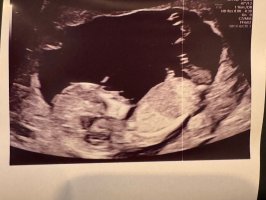

Alt så bra ut i magen i dag

8+4 og jeg kan se at lille har vokst den siste uka, oppgradert til bamsemums-stadiet

de har ikke tatt noen målinger annet enn å bekrefte liv og forventet hjertefrekvens, men akkurat nå er det det viktigste siden det ikke foreligger noen bekymringer rundt babyen